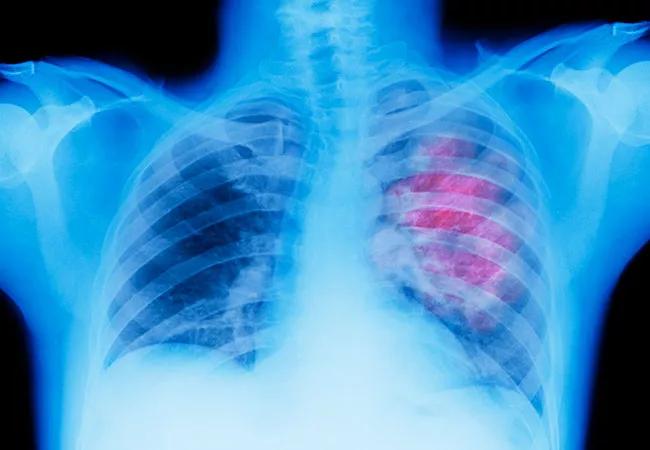

Higher-dose Stereotactic Radiotherapy Achieves Better Control for Many Aggressive Lung Tumors

Stereotactic body radiotherapy (SBRT) made it possible to treat lung cancer patients with high doses of radiation in as few as one to five sessions. But do patients do better with five sessions, or three? And can clinicians really achieve tumor control with a single session? A large study by Cleveland Clinic physicians offers new guidance.

The retrospective study presented at the annual meeting for the American Society for Radiation Oncology found that lung tumors that were larger or more aggressive benefitted more from higher-dose radiation over fewer sessions. Notably, the researchers also found that a single high-dose session was as effective in achieving control as other regimens.